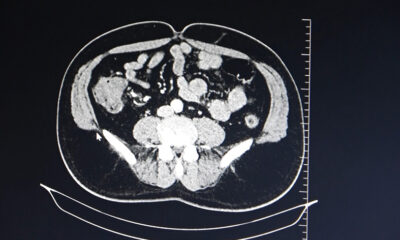

Sağlık8 ay önceİdrardaki kanama kanser habercisi

Sağlık9 ay önceKolon kanserine karşı uyarı

Sağlık9 ay önceErken teşhis hayat kurtarır